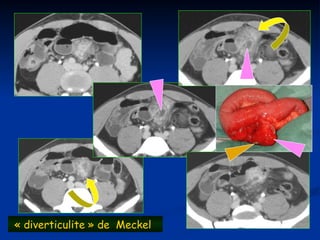

 Diverticulite de meckel , du colon droit

« diverticulite » de Meckel